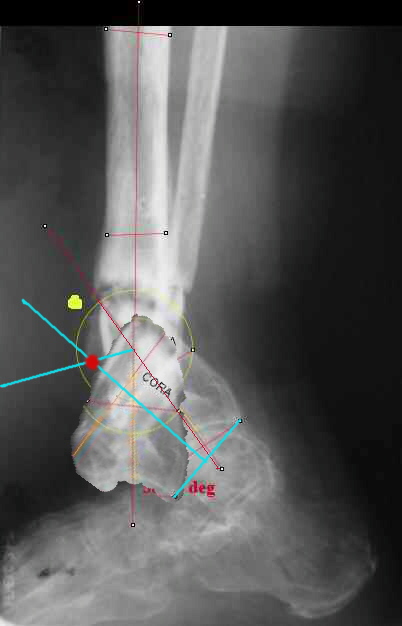

I played with your image using some orthopedic software we have been developing for digital

image analysis.

What you see marked up is the intercept of two mid-line tool centre lines, used to define the CORA. An angle tool gives the angular deformity and a circle tool is applied to show that a correction around the CORA through the old # will restore alignment without much translation.

Maybe my "embedded software" is obsolete but it hints me to place hinges at the yellow point - this must result with alignment and some lengthening without translation. What do you think?

I think that if you locate the hinge at that site and then you rotate the foot about this point with out distraction you will be perfectly lined up. If you distract in the axis of the proximal tibia then rotate, it should still work (the hinge should still be located in the mid tibial axis). But, if you distract out of that axis then you will get translation. Does that make sense?

I looked at your image. I presume your yellow marker is the hinge axis? I think this should be at the CORA.

The right hinge point to simultaneously correct deformity and shortening will be the crossing point between the bissectrice of the complementary

angle of deformity and the perpendicular at the middle of the line connecting the departure and arrival place of one point of the bone structure you are correcting (see sketch.